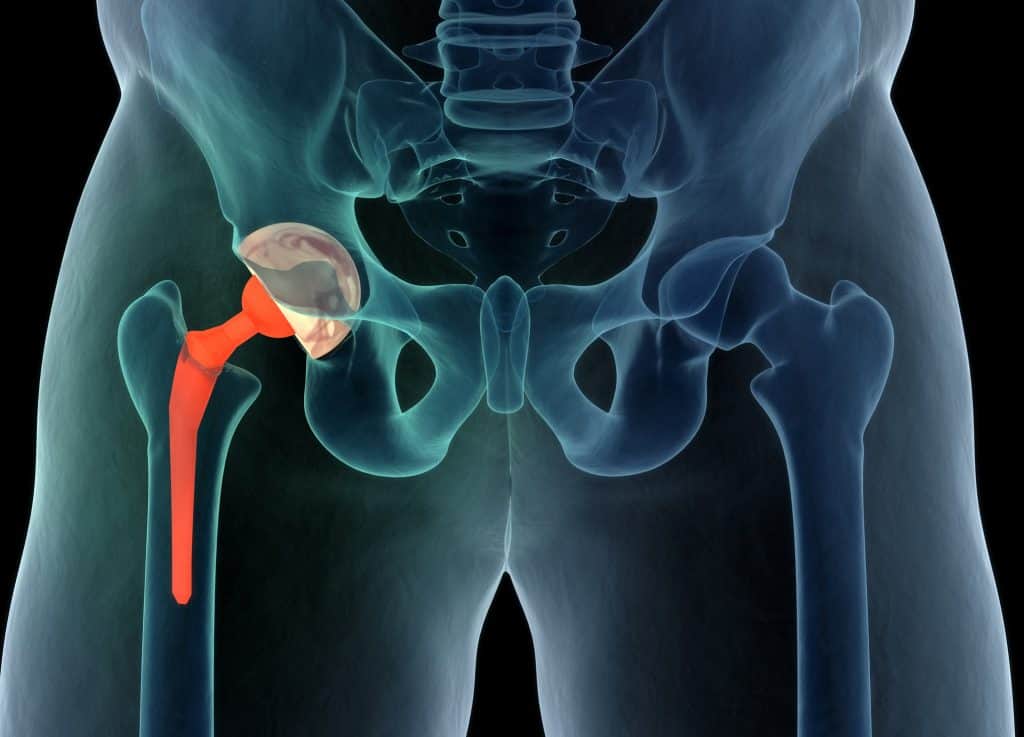

Some pain relievers such as NSAIDs and Acetaminophen can help with pain associated with OA, however there is currently no drug proven to modify the disease process of OA.17 Corticosteroids are also sometimes used for painful OA. These can be helpful in the short-term, but studies have found that people who do physiotherapy have better outcomes at one year with pain and function than those who get an injection.18 Physiotherapy for OA focuses on tailored exercises, but can also include hands-on manual therapy to help with initial pain levels and function of the joints. Surgery is a great option for someone who has progressed to that stage. If this is something you are considering, check out our articles on hip and knee replacements.